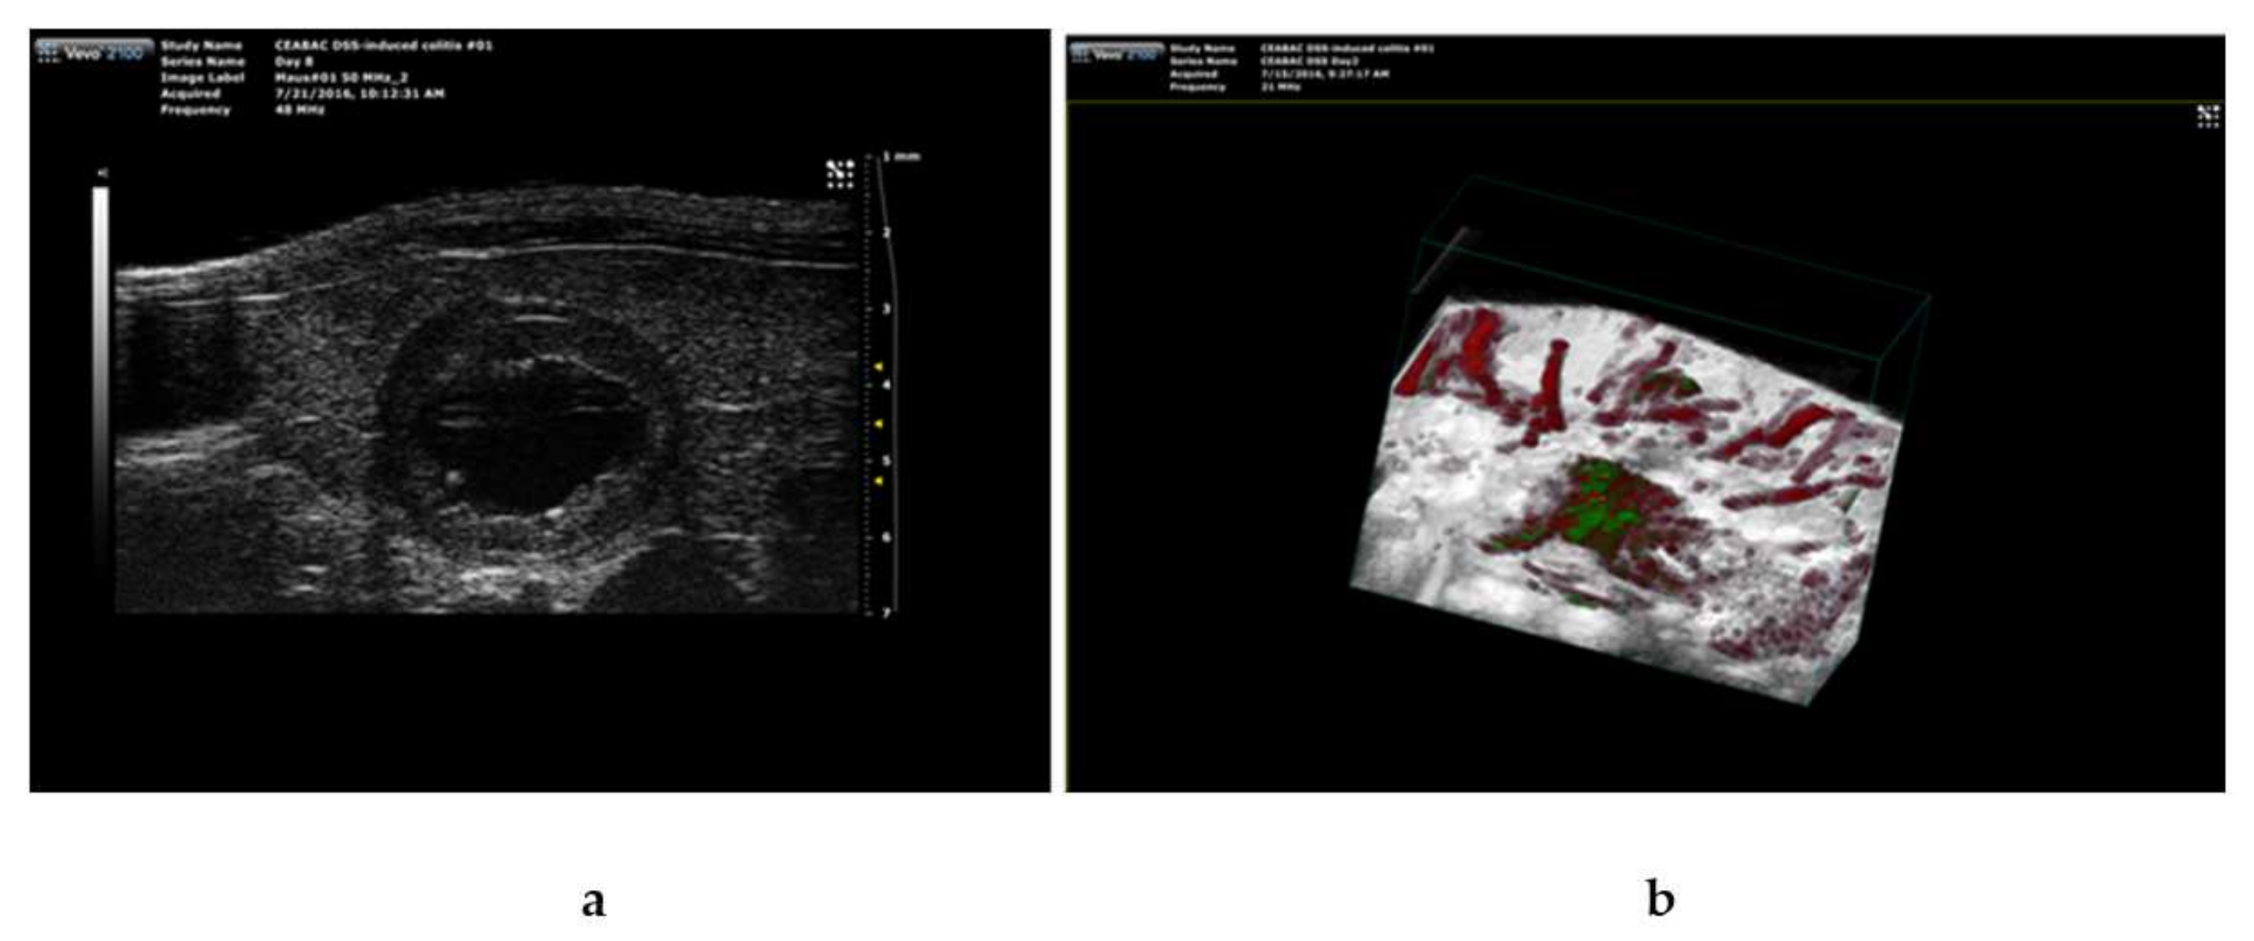

3.3. Liposomal Targeting In Vivo